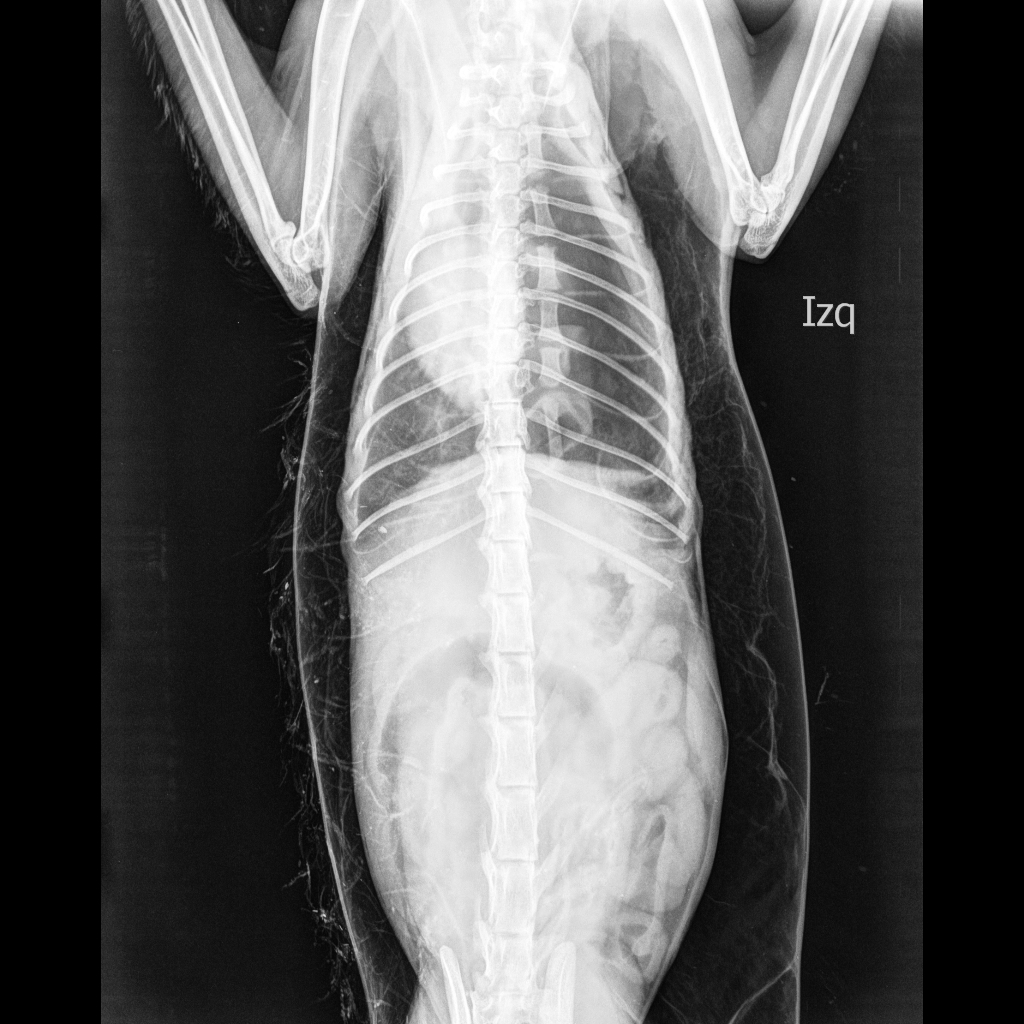

Diversos casos son fácilmente diagnosticados por los signos característicos de la condición.[1] En otros se dificulta el diagnóstico debido a que los signos son imperceptibles.[12] Se utiliza la imagen médica para diagnosticar o confirmar la condición. En radiografías torácicas, el enfisema se observa como estriaciones radiolucentes en el área del músculo pectoral mayor. El aire en los tejidos subcutáneos puede interferir con la radiografía torácica, por lo tanto puede esconder condiciones graves como el neumotórax.[16] También puede reducir la efectividad del ultrasonido torácico.[24] Por otr lado, dado que el enfisema es visible en los rayos X torácicos antes que el neumotórax, su presencia puede utilizarse para inferir esta última lesión. Esta condición también se observa en las tomografías computarizadas como zonas oscuras. Normalmente, al ser una técnica muy sensible, es posible encontrar el lugar exacto desde donde el aire ingresa a los tejidos blandos.[12]